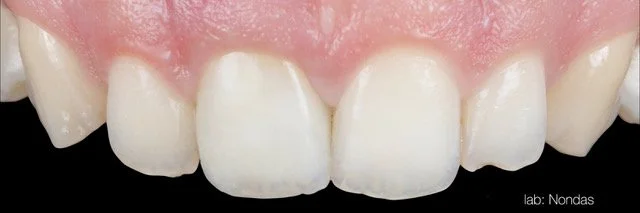

• Atsevišķi zobu implanti estētiskajā zonā

• Implanta dizaina un savienojuma, abatmentu izvēles un ārstēšanas procesa nozīme

• Transmukozālās kontūras veidošana ap implantiem: izpratne, dizains un klīniskā pieeja

16.00 - 18.00 | Tūlītēja implanta ievietošana estētiskajā zonā (#21) un mīksto audu pārvaldība; Digitāli vadīta tūlītēja implanta ievietošana zoba vietā nr. 12 ar horizontālu GBR un CTG, izmantojot diska perforācijas (disc-punch) kaula transplantācijas tehniku. (praktiskās nodarbības Proimplant apmācību telpā Türi 10C Tallinā)